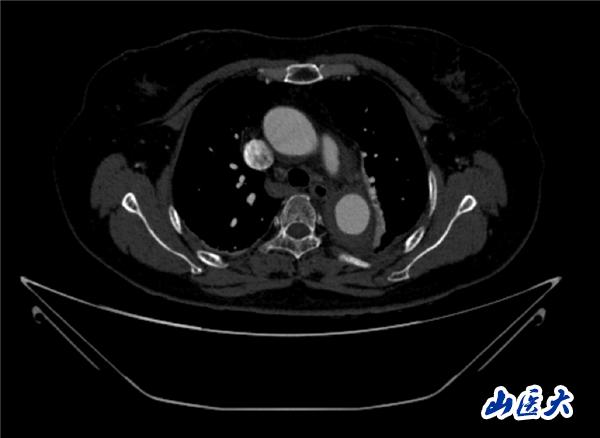

术中造影结果

首例患者是一位55岁的女性,她患有高血压约2年时间,平时也会规律服用多种降压药,但血压控制始终不尽人意。2023年4月下午,她出现不明原因的头痛,在家拔罐缓解少许便未到医院就医,次日凌晨突感胸闷、胸背疼痛伴有呼吸困难等症状、家人急忙拨打了120,把患者送入医院急诊科进行救治,医生在急诊科行胸腹主动脉CTA时,显示主动脉弓部-降主动脉及腹主动脉壁间血肿,遂收治入医院血管外科,患者入院10天后复查血肿仍未有改善,依然伴有胸背部疼痛等不适,如不进一步处理,可能发展为夹层危及生命,患者及家属经过与医生团队了解沟通,决定进行创伤小、恢复快的介入手术治疗。张玮教授、符伟国教授、董红霖教授及其血管外科团队(闫盛、常文凯、田琴琴)共同商讨手术方案,最终确定使用Zipper™一体式主动脉弓覆膜支架系统,行胸主动脉覆膜支架腔内隔绝术+无名动脉、左颈总动脉、左锁骨下动脉分支重建术为患者进行治疗。董红霖教授及其血管外科团队根据患者术前头颅CT平扫提示双侧侧脑室旁缺血灶,血压控制不稳定,属夹层壁间血肿非典型夹层等风险点,制定了完整的手术方案,术中经股动脉置入Zipper支架主体,经预留导丝超选无名动脉,并确保主体支架对位准确,顺利置入左颈总动脉、左锁骨下动脉支架,重建弓上三分支。手术过程非常顺利。术后观察主动脉及分支覆膜支架定位准确;无内漏;分支支架通畅,动脉供血正常。